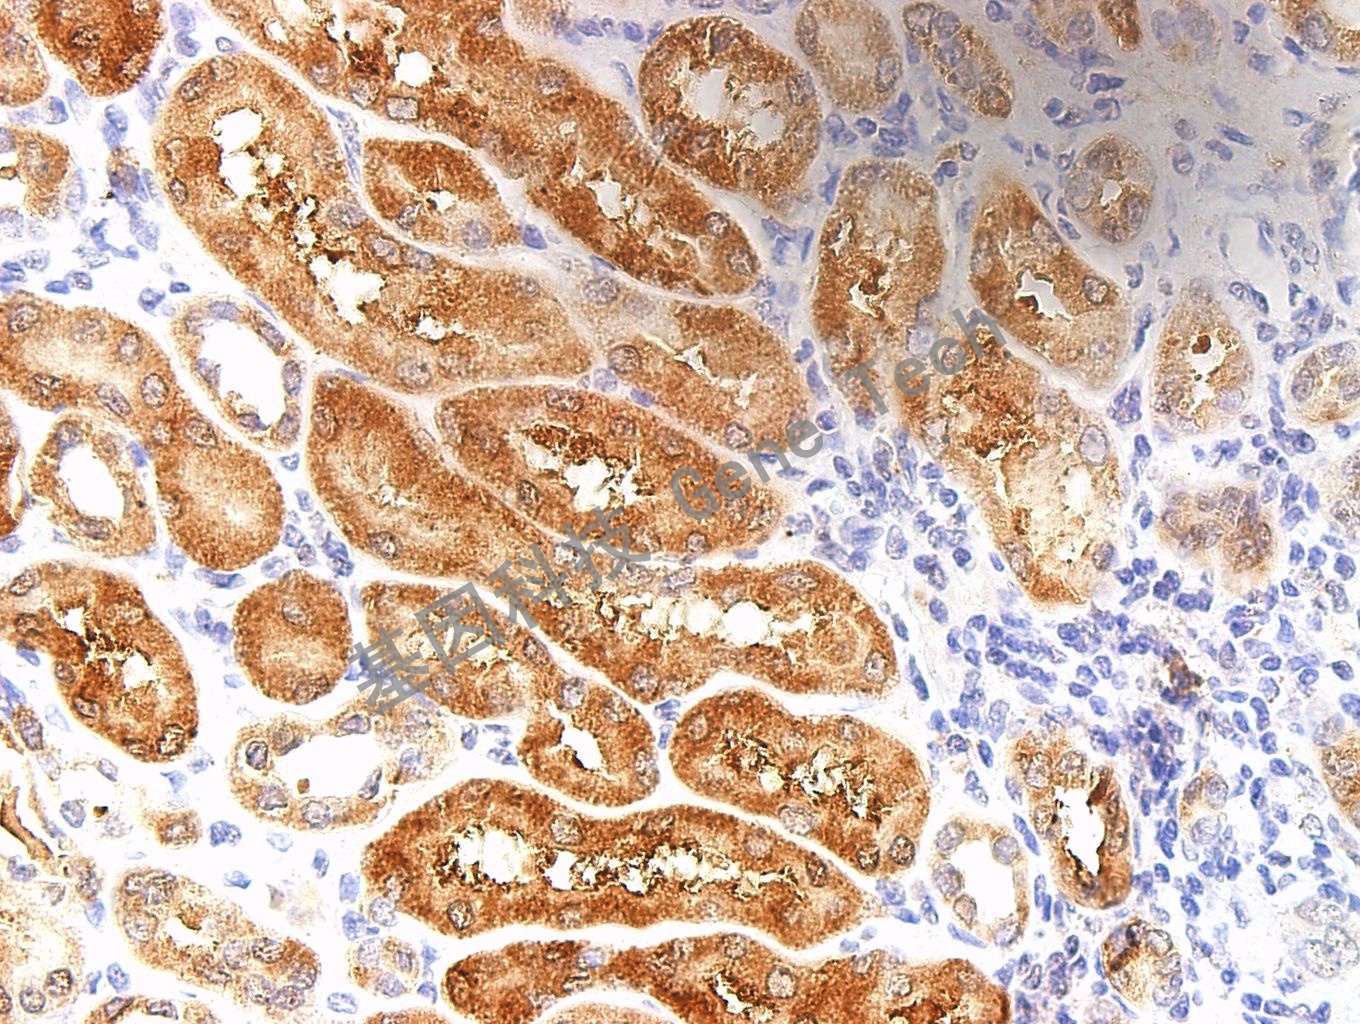

RCC 石蜡切片,用RRM1(GT2217)染色,细胞浆阳性 ,DAB显色。(10×)

RCC 石蜡切片,用RRM1(GT2217)染色,细胞浆阳性 ,DAB显色。(40×)